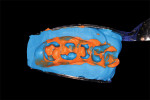

As an in-office CAD/CAM restorative system, E4D Dentist possesses the unique feature of being able to scan an impression (Figure 5) and then create a 3D model for restorative fabrication. This is especially helpful for patients who have a hard time staying open or for more difficult areas in the posterior regions of the mouth. This increases the appointment time by only several minutes at most, while at the same time minimizing clinician frustration and patient discomfort. After the optical images of the impression were accomplished, the restorations were then fabricated using the E4D Dentist library of teeth (Figure 6). After the restorations were milled, they were then tried in to verify fit and contact strength. These factors being acceptable, the restorations were then stained and glazed and placed in a porcelain oven to maximize the esthetic properties, inherent strength, and fracture resistance of the porcelain blocks (Figure 7).8